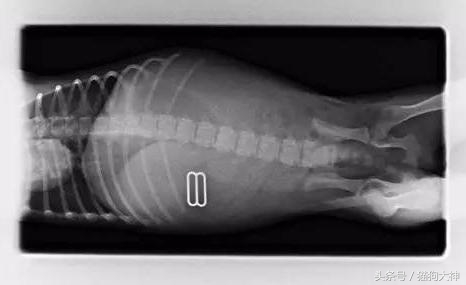

前两天,一只小腊肠去打疫苗,却意外捡回了一条命!因为在打疫苗过程中,主人和医生聊天说狗狗拆了自己的键盘,结果好多零件都找不到了,主治医师一听不对,赶紧安排狗狗拍片和手术。

这就是从狗狗胃里取出的零件,几乎塞满了小家伙的胃,再晚发现可能就要悲剧了。